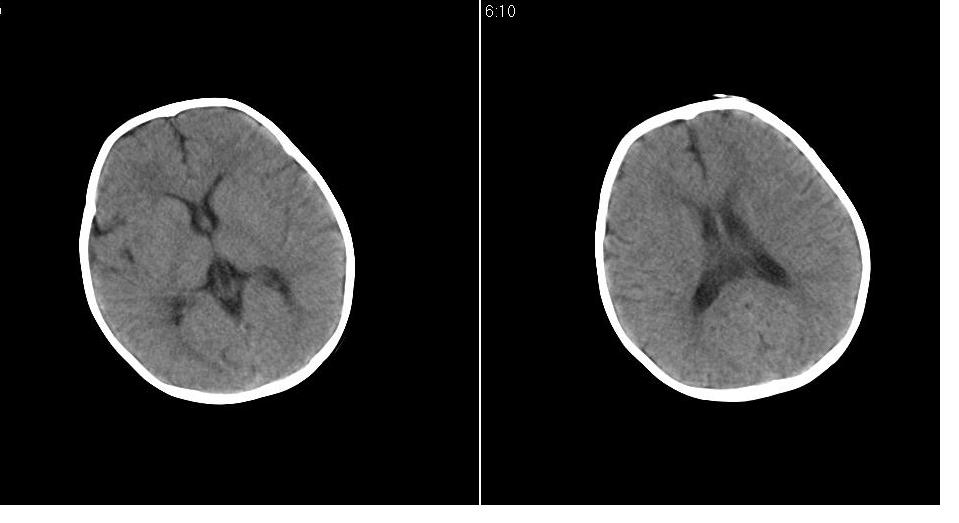

男 1岁,外伤就诊。智力正常,骨窗正常。

正常变异,大枕大池。鉴别:蛛网膜囊肿、双侧小脑发育不良。

蛛网膜囊肿一般是封闭的空间,张力较大,临近颅骨一般受压变薄。本例支持大枕大池

大枕大池与蛛网膜囊肿的主要区别就是看颅骨有没有压迹,如果有的话一般考虑蛛网膜囊肿。